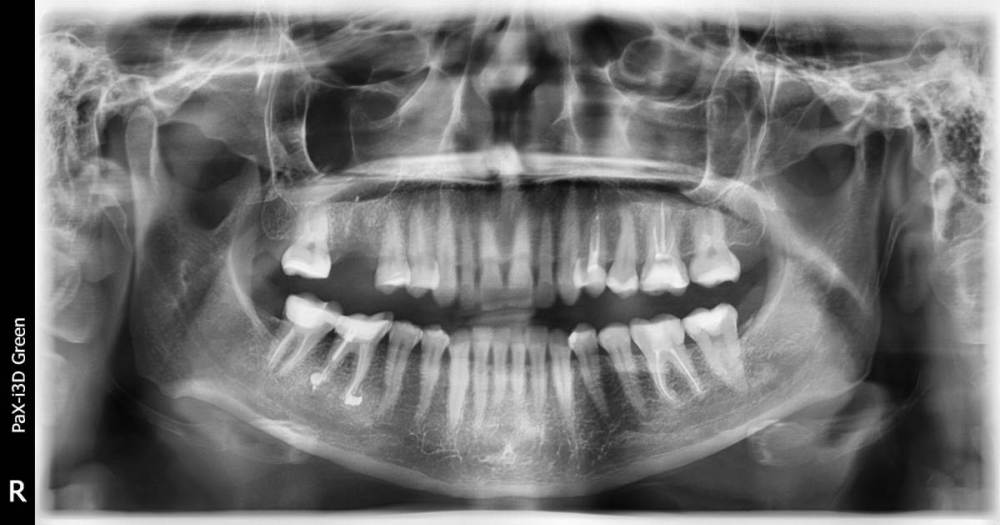

Yana-Anny Опубликовано 22 апреля, 2021 Автор Поделиться Опубликовано 22 апреля, 2021 (изменено) Удалось выпросить снимки, но боль практически утихла уже, только немного ноет челюсть. Посмотрите, пожалуйста, еще 26 зуб, диагноз гранулема на верхушке корня. Проведена ревизия каналов, временное пломбирование пастой каласепт, затем постоянное гуттаперчевыми штифтами. Постпломбировочные боли 4-й день довольно сильные. Есть ли шанс спасти зуб? Изменено 22 апреля, 2021 пользователем Yana-Anny Ссылка на комментарий

red_butler Опубликовано 22 апреля, 2021 Поделиться Опубликовано 22 апреля, 2021 по снимкам все нормально. 2.6 нужно на Кт посмотреть 1 Ссылка на комментарий